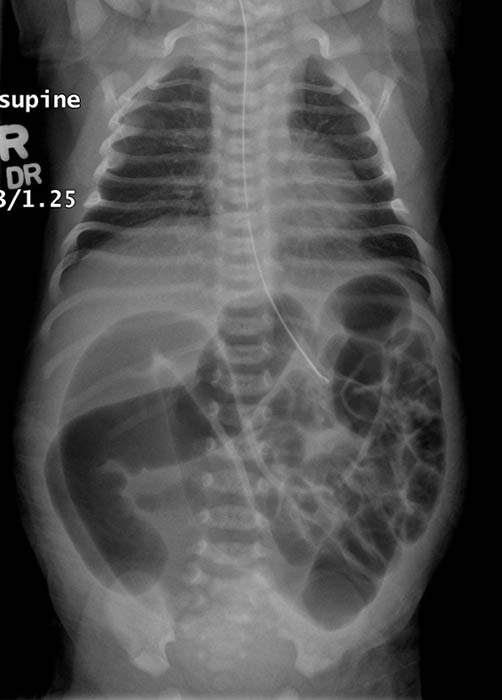

What is imperforate anus?

A congenital failure of the membrane between the rectum and anus to rupture.

What other names are used for imperforate anus?

Anal agenesis and rectal atresia.

Why does bowel obstruction occur in imperforate anus?

The rectum does not communicate with the anus.

How is imperforate anus categorized anatomically?

As high or low, depending on distance from the anus.

What associated abnormalities are common with imperforate anus?

Genitourinary fistulas.

What is the earliest sign of imperforate anus?

Failure to pass meconium. (babies first stool)

What additional signs may be present with imperforate anus?

Abdominal distension and stool in urine or vagina.

How is imperforate anus treated?

Surgical correction and fistula repair.